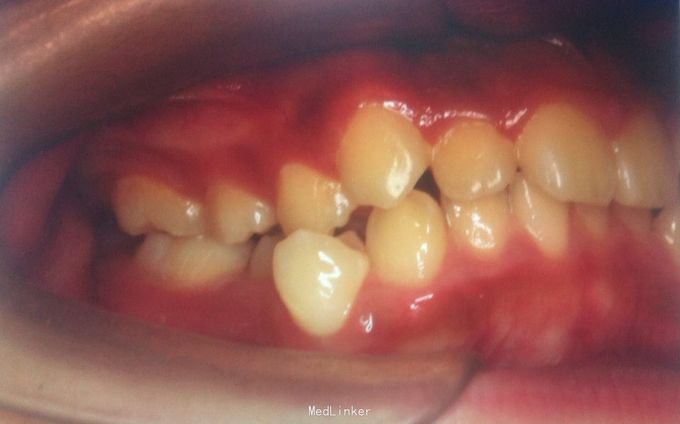

恒牙期 33,44唇侧错位 磨牙中性关系 前牙覆合2度、覆盖1度 牙列拥挤

牙列拥挤、安氏一类 拔牙矫治,拔除14、24、34、44(强支抗)排齐整平上下牙列,直丝弓矫治器,关闭拔牙间隙,矫治后前牙覆合覆盖正常,磨牙中性关系,面型略改善